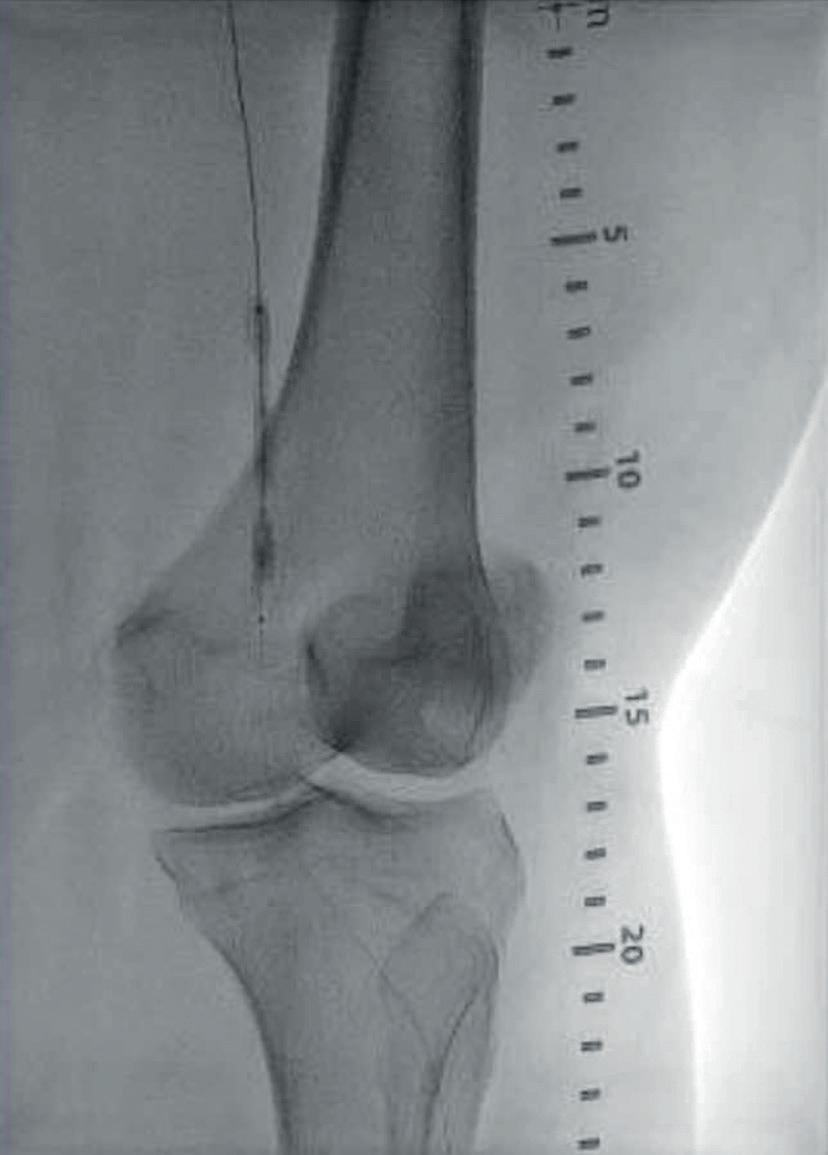

Significant life and limb gains for claudicants who stop smoking before lowerextremity bypass

LONG-TERM OVERALL survival (OS) and amputation-free survival (AFS) are outcomes that rebound in claudicants who quit smoking prior to elective surgery—and they mirror those of never smokers. But patients who do not kick the habit have significantly worse outcomes, lighting up the question: should stubbing out for good be “a requirement” before intervention?

That was the message from Rohini J Patel (University of California San Diego, San Diego, USA), who presented data at this year’s Society for Vascular Surgery (SVS) Vascular Annual Meeting (VAM 2023; 14–17 June, National Harbor, USA) on long-term outcomes in the smoking claudicant after elective lower extremity bypass. The findings were published simultaneously in the Journal of Vascular Surgery (JVS).

Patel noted that patients and vascular specialists must grasp that structured smoking cessation should be a more

prominent part of vascular office visits before and after lower extremity bypass and can “even be considered a requirement prior to elective procedures in claudicants”, a group that represents a unique non-emergent vascular patient population that can require lower extremity bypass.

Smoking is known to increase complications, including poor wound healing and coagulation abnormalities, and have cardiac and pulmonary ramifications, said Patel. “Across specialties, elective surgical procedures are commonly denied to active smokers. Given the base population of active smokers with vascular disease, smoking cessation is encouraged but is not required the way it is in general surgery,” she explained.

The research team queried the Vascular Quality Initiative Vascular

Implant Surveillance and Interventional Outcomes Network (VISION) database

over a 16-year period to tackle the question of how actively smoking claudicants fare after elective lower extremity bypass. They then carried out two separate propensity score matches on patient records that included 609 (10%) never smokers, 3,388 (55.3%) former smokers, and 2,123 (34.7%) current smokers who underwent bypass for claudication. One analysis examined the outcomes of former smokers and compared these to outcomes achieved in patients who had never smoked. The second analysis contrasted outcomes between current smokers and former smokers. The primary outcome measures included five-year OS, limb salvage (LS), freedom from target lesion reintervention (FTR) and AFS.

Health gains do not shift unless claudicants quit smoking

There were no differences recorded with respect to any of these measures between 497 well-matched pairs of former smokers and those who had never smoked. The second analysis, which focused on ascertaining outcome differences between 1,451 wellmatched pairs of current and former smokers, found that there was no

difference in LS or FTR, but revealed “a significant increase in OS and AFS” in former smokers compared with current smokers, suggesting that giving up smoking reaps rewards in terms of both limb and life preservation.

“Our study found that former smokers have better OS and AFS when compared to current smokers, while former smokers mimic never smokers at five-year outcomes for OS, LS, FTR and AFS,” Patel averred.

Patel states: “This study emphasises that we as providers must spend more time and effort working with patients to quit smoking prior to elective lower extremity bypass in claudicants.”

Limitations of the study include that the database contained no information on the duration or intensity of smoking among the study population.

According to senior author Mahmoud Malas (University of California San Diego): “Previous studies have shown that smoking cessation might not necessarily affect an immediate outcome in patients. We have found through this VISION database that even quitting one month prior to surgical intervention can change longterm outcomes.

“Former smokers do better than current smokers and former smokers mimic the results of patients who have never smoked. As vascular surgeons, we need to play a more active role in these discussions with patients in the clinic.”